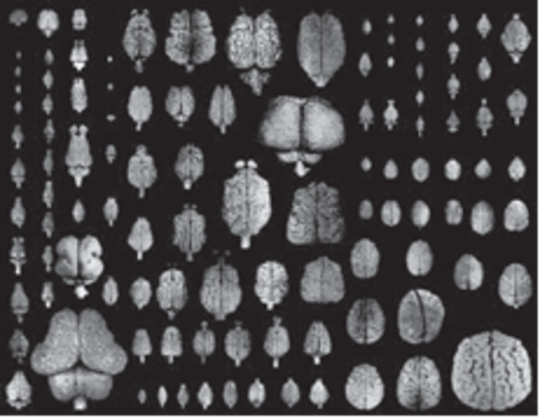

Ó®ÆýÎà¤ÎǾ¤ò¸«Èæ¤Ù¤Æ¤ß¤ë¤È¡¢¤³¤ì¤¬Æ±¤¸Ç¾¤Ê¤Î¤«¤È¶Ã¤¤Þ¤¹¡£¿Þ1¤Ï¡¢¤¤¤í¤¤¤í¤ÊÓ®ÆýÎà¤ÎǾ¤ò¾å¤«¤é¸«¤¿¤â¤Î¤Ç¤¹¡£°ì¸«¤·¤Æ¡¢¤É¤ì¤âǾ¤À¤È¤ï¤«¤ëÄøÅ٤ˤÏÎà»÷¤·¤Æ¤¤¤Þ¤¹¤¬¡¢¤è¤¯¸«¤ë¤È°ã¤¤¤¬¤¢¤ë¤³¤È¤¬¤ª¤ï¤«¤ê¤¤¤¿¤À¤±¤ë¤Ç¤·¤ç¤¦¤«¡£

¿Þ1¡¡¤¤¤í¤¤¤í¤ÊÓ®ÆýÎà¤ÎǾ¡Ê½Ð½ê¡ËFlorian Maderspacher, Sizing up the soul¡Çs seat, Curr Biol. 26¡Ê20¡Ë, 2016

https://doi.org/10.1016/j.cub.2016.09.066

´ðËÜŪ¤Ë¤Ï¡¢¤É¤ÎǾ¤ÎÂçǾÈé¼Á¤Ë¤â±¦Ç¾¤Èº¸Ç¾¤¬¤¢¤ê¡¢¤½¤Î²¼¤Ë¾®Ç¾¡¢¤½¤·¤ÆÀÔ¿ñ¤Ë¤Ä¤Ê¤¬¤ëǾ´´¤¬¸«¤¨¤Æ¤¤¤Þ¤¹¡£¥Ò¥È¤Î¾ì¹ç¤Ï¡¢ÂçǾÈé¼Á¤¬Èó¾ï¤Ëȯ㤷¤Æ¤¤¤ë¤¿¤á¡¢¾®Ç¾¤Ï±£¤ì¤Æ¸«¤¨¤Þ¤»¤ó¤¬¡¢´ðËÜŪ¤Ê¹½Â¤¤Ï°ì½ï¤Ç¤¹¡£

°ìÊý¡¢¥Þ¥¦¥¹¤ä¥é¥Ã¥È¤Ê¤É¤ÎÂçǾÈé¼Á¤Ë¤Ï¥·¥ï¤¬¤Ê¤¤¤³¤È¤Ëµ¤¤Å¤¤¤¿¤Ç¤·¤ç¤¦¤«¡£¹«¤Ç¤Ï¤³¤ÎǾ¤Î¥·¥ï¤¬Â¿¤¤¤Û¤É¡ÖƬ¤¬Îɤ¤¡×¤È¸À¤ï¤ì¤Æ¤¤¤Þ¤¹¤¬¡¢¤½¤ì¤Ï¸í²ò¤Ç¤¹¡£¤³¤Î¥·¥ï¤Ï¡¢ÂçǾÈé¼Á¤ÎɽÌÌÀÑ¤ÈÆ¬³¸¹ü¤ÎÂ礤µ¤Ë¤è¤Ã¤Æ·è¤Þ¤ê¤Þ¤¹¤¬¡¢¥Ò¥È¤Î¾ì¹ç¤ÏÂçǾÈé¼Á¤ò¹¤²¤¿ºÝ¤ÎɽÌÌÀѤϡ¢¿·Ê¹»æ°ìËçÄøÅ٤ȸÀ¤ï¤ì¤Æ¤¤¤Þ¤¹¡£¤½¤ì¤òƬ³¸¹ü¤ÎÃæ¤ËÆþ¤ì¤ë¤¿¤á¤Ë¤Ï¥·¥ï¤¬¤Ç¤¤Æ¤·¤Þ¤¤¤Þ¤¹¡£

ÎîĹÎà¤ÎÃæ¤Ç¤â¡¢¥³¥â¥ó¥Þ¡¼¥â¥»¥Ã¥È¤Ç¤Ï¥·¥ï¤¬¤Ê¤¤¤³¤È¤¬Í̾¤Ç¤¹¤·¡¢¥¤¥¿¥Á¤ÎÃç´Ö¤Î¥Õ¥§¥ì¥Ã¥È¤ÎǾ¤Ë¤Ï¥·¥ï¤¬¤¢¤ë¤³¤È¤¬ÃΤé¤ì¤Æ¤¤¤Þ¤¹¡£¥·¥ï¤ÎÍ̵¤È¸¤µ¤Ë¤Ï¤¢¤Þ¤ê´Ø·¸¤¬¤Ê¤¤¤È¹Í¤¨¤ÆÎɤ¤¤È»×¤¤¤Þ¤¹¡£